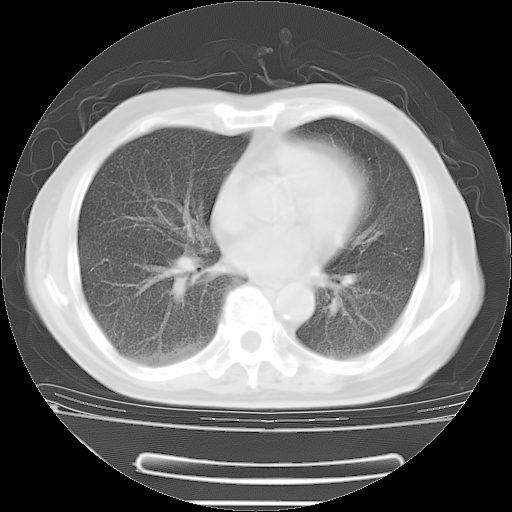

今天复查肺部CT,发现双肺广泛磨玻璃样改变。所以我把3月19日和5月9日相隔50天的肺部CT上传。请大家会诊。

2009年3月19日肺部CT片。

2009年3月19日肺部CT

大致读了系列胸部CT:纵隔窗无明显异常,肺窗:从4、27至今:主要是双肺中下野外带可见毛玻璃样改变,目前处于急性肺泡炎阶段,至于原因考虑1、结替组织或胶原血管性疾病所致?2、恶性疾病如恶组在肺部所致的表现或细支气管肺泡癌?3、药物或其它原因如肺蛋白沉着症所致肺泡炎目前不太可能?总之,明天就去请我院的呼吸科、感染科、血液科和临免专家会诊哈。